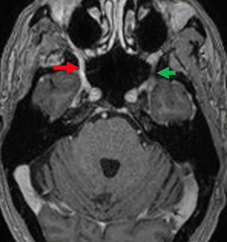

Figure 5 Magnetic resonance imaging, T1-weighted sequence with fat suppression. Axial slices showing anomalous contrast enhancement in the right foramen ovale (red arrow) when compared to the contralateral foramen (green arrow), consistent with involvement of the mandibular nerve (CN V3).

An 85-year-old male presented with a 6-month history of right hemifacial pain radiating to the ipsilateral ear, concomitantly with the onset of a skin lesion in the right malar region. He reported biopsy of a lesion in the same region 3 years ago, with local recurrence after 1 year, both resected with clear margins and a histopathological diagnosis of squamous cell carcinoma. MRI of the paranasal sinuses and brain showed a lesion consistent with tumor infiltration involving the infratemporal segment of the third branch of the right trigeminal nerve, extending to the foramen ovale and ipsilateral trigeminal cave, which was compressed (Figure 4) (Figure 5).